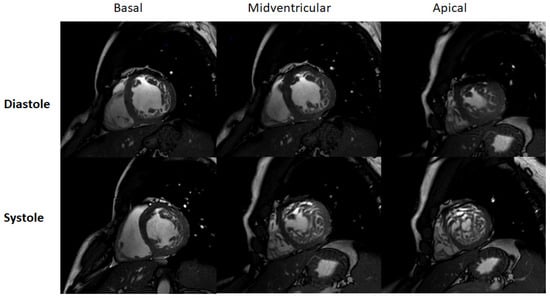

- Stacey, R.B.; Andersen, M.M.; St Clair, M.; Hundley, W.G.; Thohan, V. Comparison of systolic and diastolic criteria for isolated LV noncompaction in CMR. JACC Cardiovasc. Imaging 2013, 6, 931–940. [Google Scholar] [CrossRef]